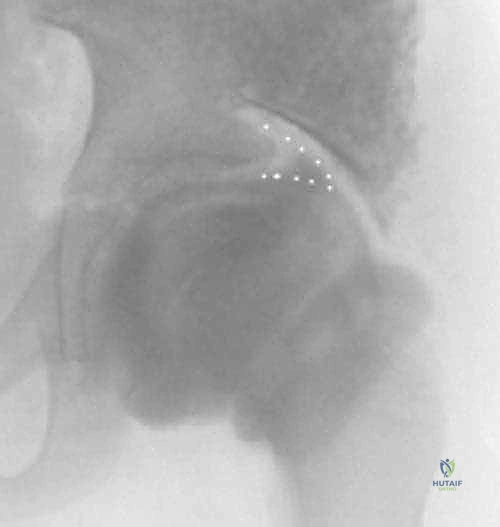

The labral support (shelf) procedure has been used in patients with Legg-Calvé-Perthes disease (or Perthes disease) in Waldenström stages of necrosis or fragmentation in which the femoral head shows deformity or is at risk for deformity6, 12 (

FIG 1

FIG 1 • Anteroposterior (AP) radiograph of an arthrogram demonstrates a labral support (shelf) in a patient with Perthes disease. The shelf supports the labrum and enlarges the acetabulum to prevent subluxation of the femoral epiphysis.